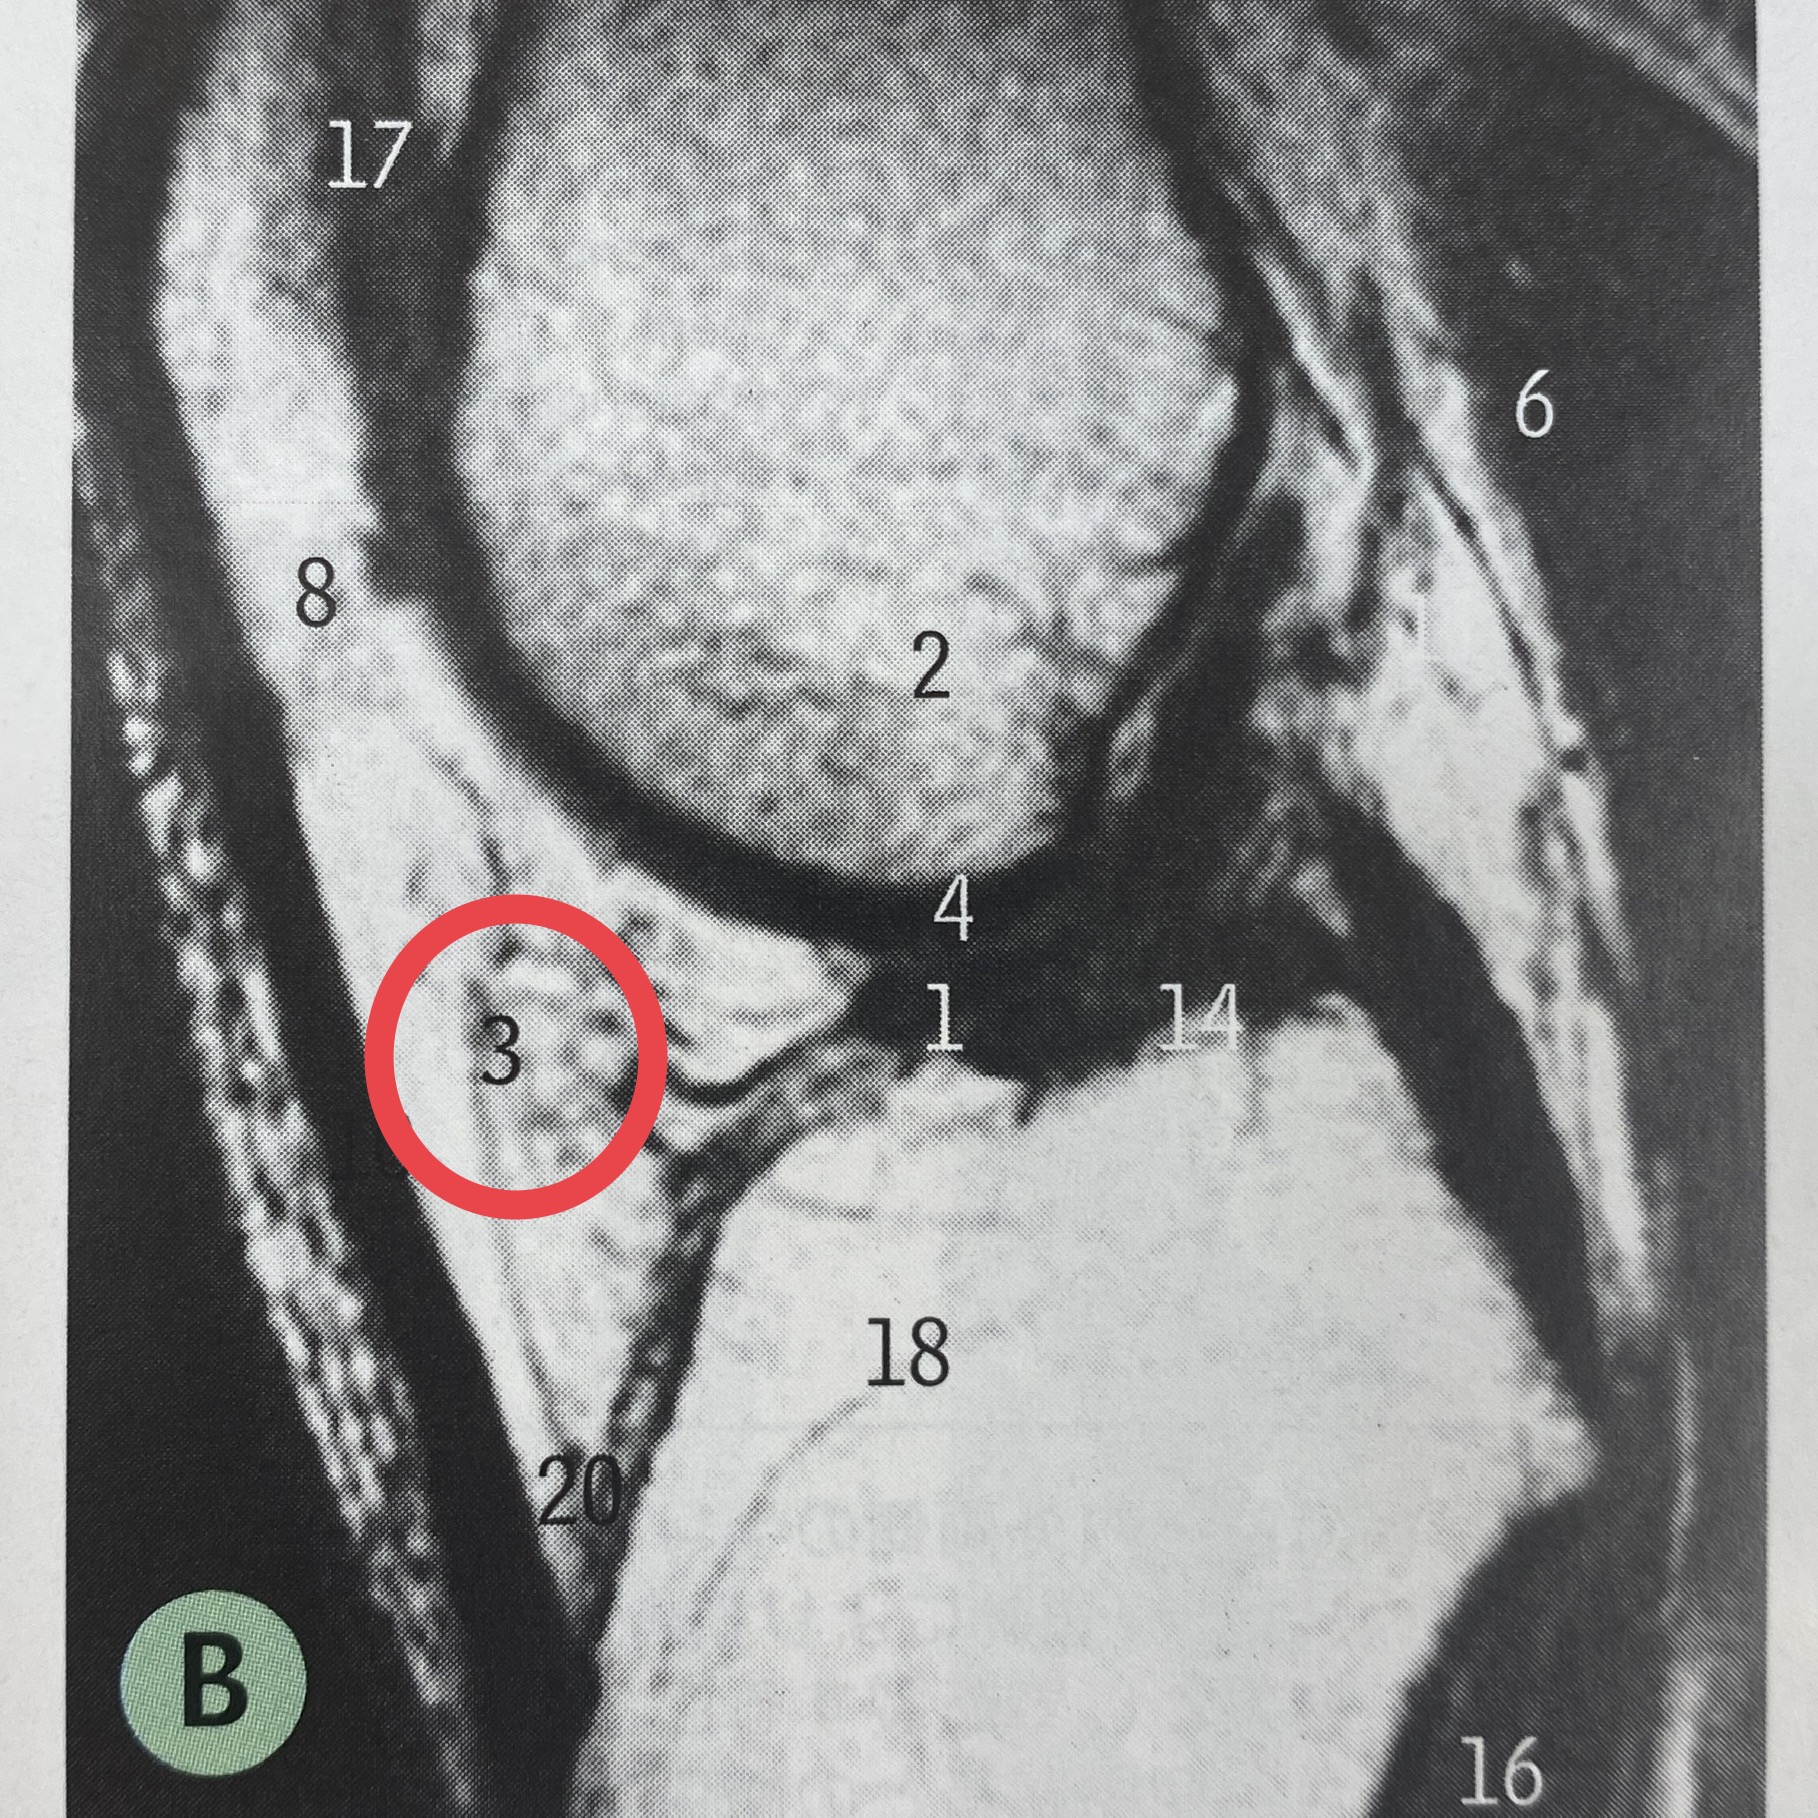

★ 膝関節の衝撃を吸収する組織である膝蓋下脂肪体は重度変形膝では委縮していることを明らかにしました!(2022.05.19) 新潟医療福祉大学 理学療法学科

膝蓋下脂肪体炎とは、膝のお皿(膝蓋骨)の下に膝蓋骨と脛骨をつなぐ腱があり、その深層に脂肪組織の膝蓋下脂肪体があります。. 立ち上がる時や膝の曲げ伸ばしに膝のお皿の下が痛くなる。. また、膝のお皿の下を押すと痛いなどの症状があり.. 実は、膝蓋下脂肪体は炎症が起きると血管がすぐにできてしまい、そしてそこに神経も一緒になって増えます。 私も今までこの「ひざ前方の痛み」の患者さんを治療してきました。 10代や20代の若い方が多いです。 このような方は、軟骨にも異常がなく、半月板にも異常がなく、精神的な面が原因ではとして、お医者さんからも家族からも「本当に痛いの? 」とうがった目で見られてしまいます。 ところがこれは、「不要な血管が痛い」という観点からみると、膝蓋下脂肪体が痛みの原因になっていることは一目瞭然な場合があります。 そうであれば、治療法は、「運動器カテーテル治療」が良いです! 治療については モヤモヤ血管について を参考にしてください。